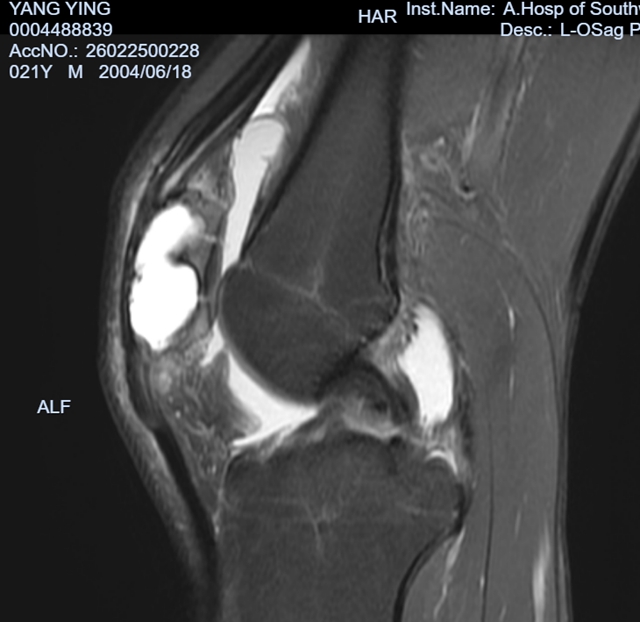

图1:术前的膝关节CT及磁共振检查,清晰显示髌骨肿瘤及病理性骨折

结合杨颖的情况和当地的检查结果,医生最终明确了问题:一是左侧髌骨因为肿瘤引发了病理性骨折,二是髌骨上确实长了骨肿瘤。